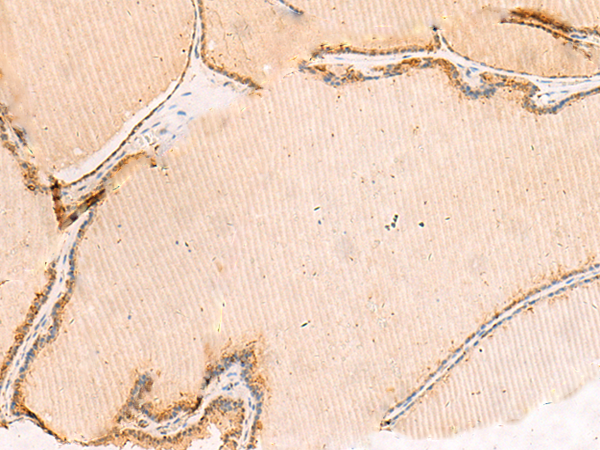

IHC positive control: |

Human thyroid cancer |

IHC Recommend dilution: |

50-300 |